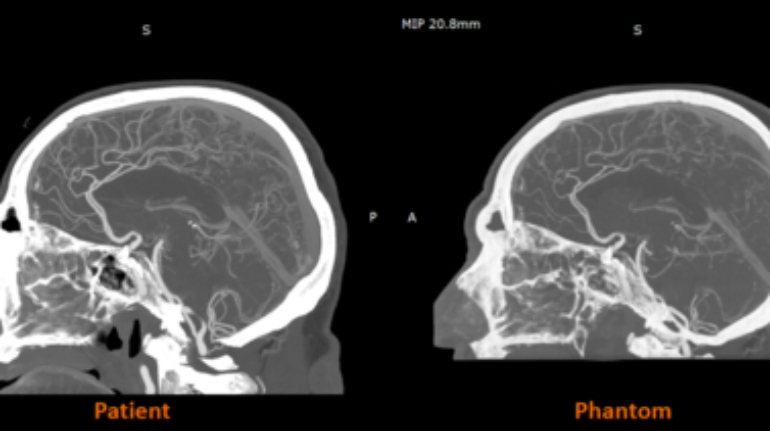

3D printer OEM Stratasys has announced that its RadioMatrix radiopaque 3D printing material is now fully commercially available in the United States. Previously deployed in limited settings, the material can now be widely used by healthcare providers, medical device manufacturers, and research institutions for advanced medical imaging, education, and training purposes.